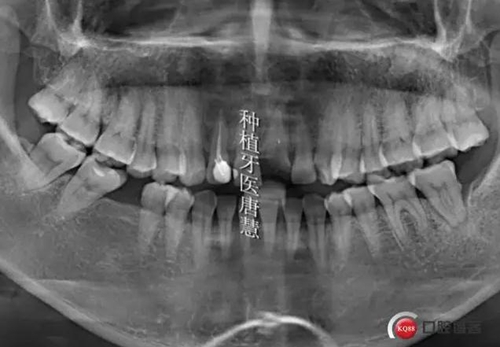

患者白XX,護士,上前牙數(shù)年前樁冠修復(fù),一天前折斷,來診,要求不能有空牙期

查見21根折,上前牙2-2樹脂貼面修復(fù),邊緣不密合,繼發(fā)齲,治療計劃:1、上前牙美學(xué)修復(fù),DSD設(shè)計,21種植,臨時修復(fù)。2、21冠延長后樁冠修復(fù),但美觀效果不理想

術(shù)前曲斷